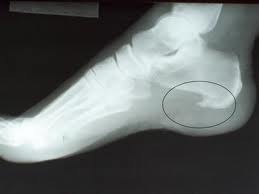

القدم هي عماد الجسم وهذا الجزء قد يهمله كثير من الناس فهو بذلك عرضه للاصابه بامراضها المختلفة ومن ضمنها…الشوكة العظمية وهو التهاب في الرباط الذي يحمي اخمص القدم وتظهر الشوكة العظمية في الكعبين ويشعر المريض بها عند المشي او بمجرد الوقوف على القدم حيث يشعر بان هناك العديد من الدبابيس المغروزة في لحمه وهذا الالم الناتج عن وجود الشوكة العظمية في احد كعبيه او كلاهما…. اسباب الشوكة العظمية :اسباب ظهور الشوكة العظمية وهو نفس اسباب ظهور العديد من امراض القدم مثل الزيادة المفاجئة في الوزن كالحمل وارتداء الاحذية الضيقه او ذات الكعب العالي المشي او الوقوف طويلا او السير حافي القدمين او الضغط كثيرا على منطقة الكعبين او السير الغير منتظ فهذه الاسباب جميعها تؤدي الى العديد من الامراض وليس الشوكة العظمية فحسبالوقاية من الشوكة العظمية :الوقاية من حدوث التهاب او بروز الشوكة العظمية في الكعبين يتم بالاهتمام ومراعة منع اسباب حدوثها من الاساس علاج الشوكة العظمية :-الحصول على الراحه حتى يخف الضغط على الكعبين-استخدام أحذية مريحة مزودة بدعامة لقوس القدم ووسادة للكعب لتخفيف الضغط-استخدام بعض أنواع الأجهزة التقويمية التي تضاف إلى الحذاء لزيادة قوس القدم للأشخاص الذين يعانون من تسطح القدم-يمكن استعمال كمادات من الماء البارد او الثلج موضعياً لتخفيف الالم في حالة كونه شديداً.-يحتاج بعض المصابين الى حقن موضعية في المنطقة الملتهبةلتخفيف حدة الالتهاب-يحتاج بعض المرضى المصابين بشوكة الكعبلإزالتها جراحياً في حالة عدم استجابتها لطرق العلاج السابقة.الشوكة العظمية تحت الاشعة (السينية):الصورة التالية توضح شكل الشوكة العظمية تحت الاشعة والمعنى من ذلك ان الشوكة العظمية تختلف عن المسمار العظمي اي انها لا تظهر فوق سطح الجلد بل يشعر بالالم الناجم عنها فقط بخلاف مسمار اللحم الذي يظهر فوق سطح الجلد ولا يظهر بالاشعة

دراسات الشوكة العظمية :العلاج الطبيعي مفيد للمصابين بالشوكة العظمية :الدكتورة هبه محمد على أخصائية العلاج الطبيعى، قائلة: إن الشوكة العظمية فى كعب القدم تكون عبارة عن نتوء عظمى فى كعب القدم، وتتسبب فى حدوث آلام مبرحة أثناء المشى أو الوقوف على القدم، ويكون ظهور هذا النتوء مصاحباً لالتهاب فى وتر اكيلس فى مؤخرة القدم، وكذلك التهاب فى اللفافة الغشائية المبطنة لأسفل القدم، وتنتج هذه الشوكة من زيادة حمض اليوريك فى الجسم وترسبه فى أسفل القدم مع كثرة المشى والتحميل عليها، بالإضافة إلى أن الشوكة العظمية تنتج من زيادة الوزن وعدم قدرة القدم على تحمل وزن الجسم، ومن ثم لابد من إنقاص الوزن واتباع تعليمات الطبيب فى كيفية تقليل حمض اليوريك فى الجسم، كما يجب عدم ارتداء الأحذية ذات الكعب العالى بالنسبة للسيدات خاصة عند المشى لمسافات طويلة.وتشير الدكتورة هبه إلى أن هناك وسائل علاجية للشوكة العظمية من خلال العلاج الطبيعى، وذلك باستخدام أجهزة الموجات فوق الصوتية وأجهزة الليزر لتقليل الالتهابات والآلام، وكذلك استخدام أجهزة التنبيه العضلى لتقوية العضلات المحيطة بالقدم، مع عمل تمارين تقوية وإطالة للغشاء المبطن لأسفل القدم مع تعليم المريض كيفية التحميل الصحيح على القدم أثناء المشى أو الوقوف لمدة طويلة.الشوكة العظمية ناتجة عن التهاب مسمار القدم أشارت بعض الدراسات إلى أن 1 – 2.5% من سكان العالم يشتكون من هذه الآلام كل سنة. والأربطة الموجودة تحت عظام القدم تتعرض لضغوط شديدة عند المشي والوقوف كونها تقع تحت عظام القدم القاسية في الأعلى والأرض في الأسفل ولذلك فهي عرضة لأمراض الإجهاد المزمن والالتهابات التي قد تؤدي مع مرور الوقت إلى ترسب كميات صغيرة من الكالسيوم في طرف هذه الأربطة مكونة نتوءا عظميا صغيرا يظهر في الأشعة السينية يطلق عليه البعض الشوكة العظمية، وهو ما يعرف عند كثير من الناس بمسمار القدم أو مسمار الكعب heel spur. ويبدأ الالتهاب حاداً، وإذا لم يعالج يتحول إلى التهاب مزمن cronic fascities. والمسمار العظمي الذي تراه في الصورة الشعاعية (الأشعة السينية) ناجم عن الالتهاب في الرباط وعن مسمار القدم، وليس سببا له.